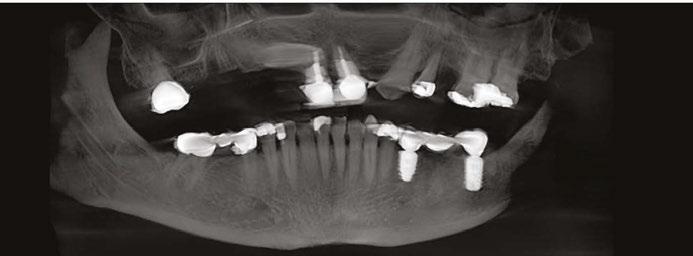

This is the presentation of the restoration of a 78-year-old male with multiple complicating factors.

Mr. Z has a skeletal Class III malocclusion. He has never received orthodontic treatment. The CBCT shows tooth No. 6 is present but horizontally impacted (Figure 4).

Based on age of patient, health history, and presence of the impacted canine, the patient was sent to an oral surgeon for evaluation. The initial consultation asked the surgeon to consider removal of impacted tooth No. 6 and placement of bone graft as a prelude to restoring site 2-7 with an implant-supported fixed bridge (Figures

Close inspection of the CBCT shows tooth No. 6 is ankylosed. The oral surgeon indicated extraction of tooth No. 6 would require block resection of bone with the tooth. The resulting defect would have required extensive bone grafting

added time and cost to this case.

On the day of surgery, the patient had MegaGen AnyRidge® implants placed at the following sites under local anesthesia:

• Tooth No. 7: trans-canine placement of 4.0 mm x 13 mm

• Tooth No. 3: 5.0 mm x 7.0 mm with small crestal approach sinus graft

• Tooth No. 13: 4.0 mm x 10.0 mm implant

Figures 7 and 8: Healing abutments in place Figure 4: Pretreatment panoramic x-ray. Note position of maxillary right canine Figures 5 and 6: Pretreatment CBCT scan with treatment planning software. Virtual implant placement at site 10 shows thin buccal bone. Buccal bone graft was provided at time of surgery Figures 9 and 10: Porcelain-on-metal framework ready for delivery

2. Paton G, Fuss J, Goss AN. The transmandibular implant: a 5- and 15-year single-center study. J Oral Maxillofac Figure 14. Post implant placement. This CBCT shows implant at site 10 through the impacted canine. Implant at site 3 was placed right against the sinus floor Figures 13A and 13B: 13A. Trans-mandibular dental implants. 13B. Subperiosteal implants Figure 11: Surgical site on day of surgery Figure 12: Implant placement of tooth No. 7 with buccal bone graft